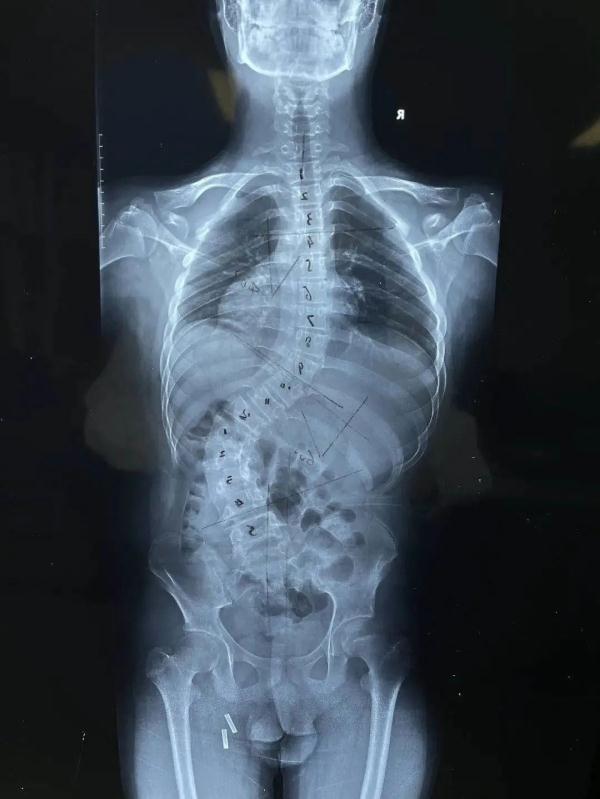

脊柱侧弯十度图片

脊柱侧弯十度图片,脊柱侧弯10度外观图

脊柱侧弯10度外观图

脊柱侧弯图片

10度脊柱侧弯图

脊柱侧弯